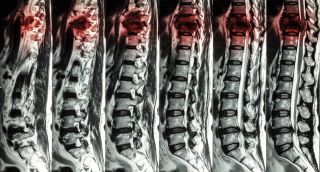

Lesión medularVarios estudios publicados en 2025 exploraron nuevas terapias para la regeneración de la médula espinalVarios estudios científicos publicados a lo largo de 2025 analizaron nuevas estrategias terapéuticas dirigidas a la regeneración de la médula espinal tras una lesión medular, una de las principales causas de paraplejia, mediante enfoques que incluyen fármacos, activación de células madre internas y trasplantes celulares en fases experimentales y clínicas, según la información facilitada por el grupo de información científica 'Nature'